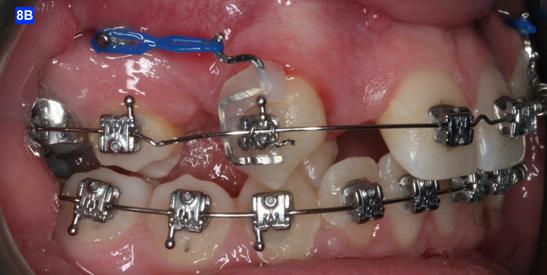

Finally, after 21 months of treatment, the patient and the parents consented to the odontectomy of the maxillary first bicuspids. The informed consent forms for the extractions and placement of TADs were signed by the parent, and all questions were answered. Risks, benefits, alternatives, and the result of no treatment at all were reviewed. Immediately after the odontectomy of #14(5) and #24(12), 1.6 x 8.0 mm AnchorPro (OrthoOrganizers) TADs were placed just mesially to the maxillary second bicuspids.6 In office power arms (a .018 x.025 SS) were fabricated and bonded to the buccal surface of the maxillary cuspids, just above the bracket.7 The purpose of the power arm is to place the applied force as close to the center of resistance of the tooth as possible. In this manner the line of action (power hook to the TAD) is parallel to the occlusal plane. The source of the force is an EC, and it must be replaced at least bi-weekly. Both arches had a .018 SS arch wire. There was a small off-center bend (tip-back, gable bend) “V” pointing occlusally, mesial to the maxillary second bicuspids.8 The purpose of this bend is to keep the roots parallel during the translation of the cuspids. There was a small OCS between #21(9) and #23(11) to shift the maxillary midline to the right. Another OCS was placed between #32(23) and #34(21) to facilitate the alignment of the mandibular left cuspid (Figure 8-A, B, C, D).

Figure 8A: TADs in situ, frontal view 8B: TAD in situ, right lateral view 8C: TAD in situ, left lateral view 8D: Power arms Figure 9A: Maxilla, occlusal view 9B: Maxilla, occlusal view 9C: Maxilla, occlusal view Figure 9D: After the removal of the Hyrax, occlusal view Figure 10A: Center bend “V” pointing gingivally Figure 10B: OCS between the cuspids and the central incisors Figure 10C: Composite build-ups on the mandibular first molars Figure 10D: Adrian “U” bend spring